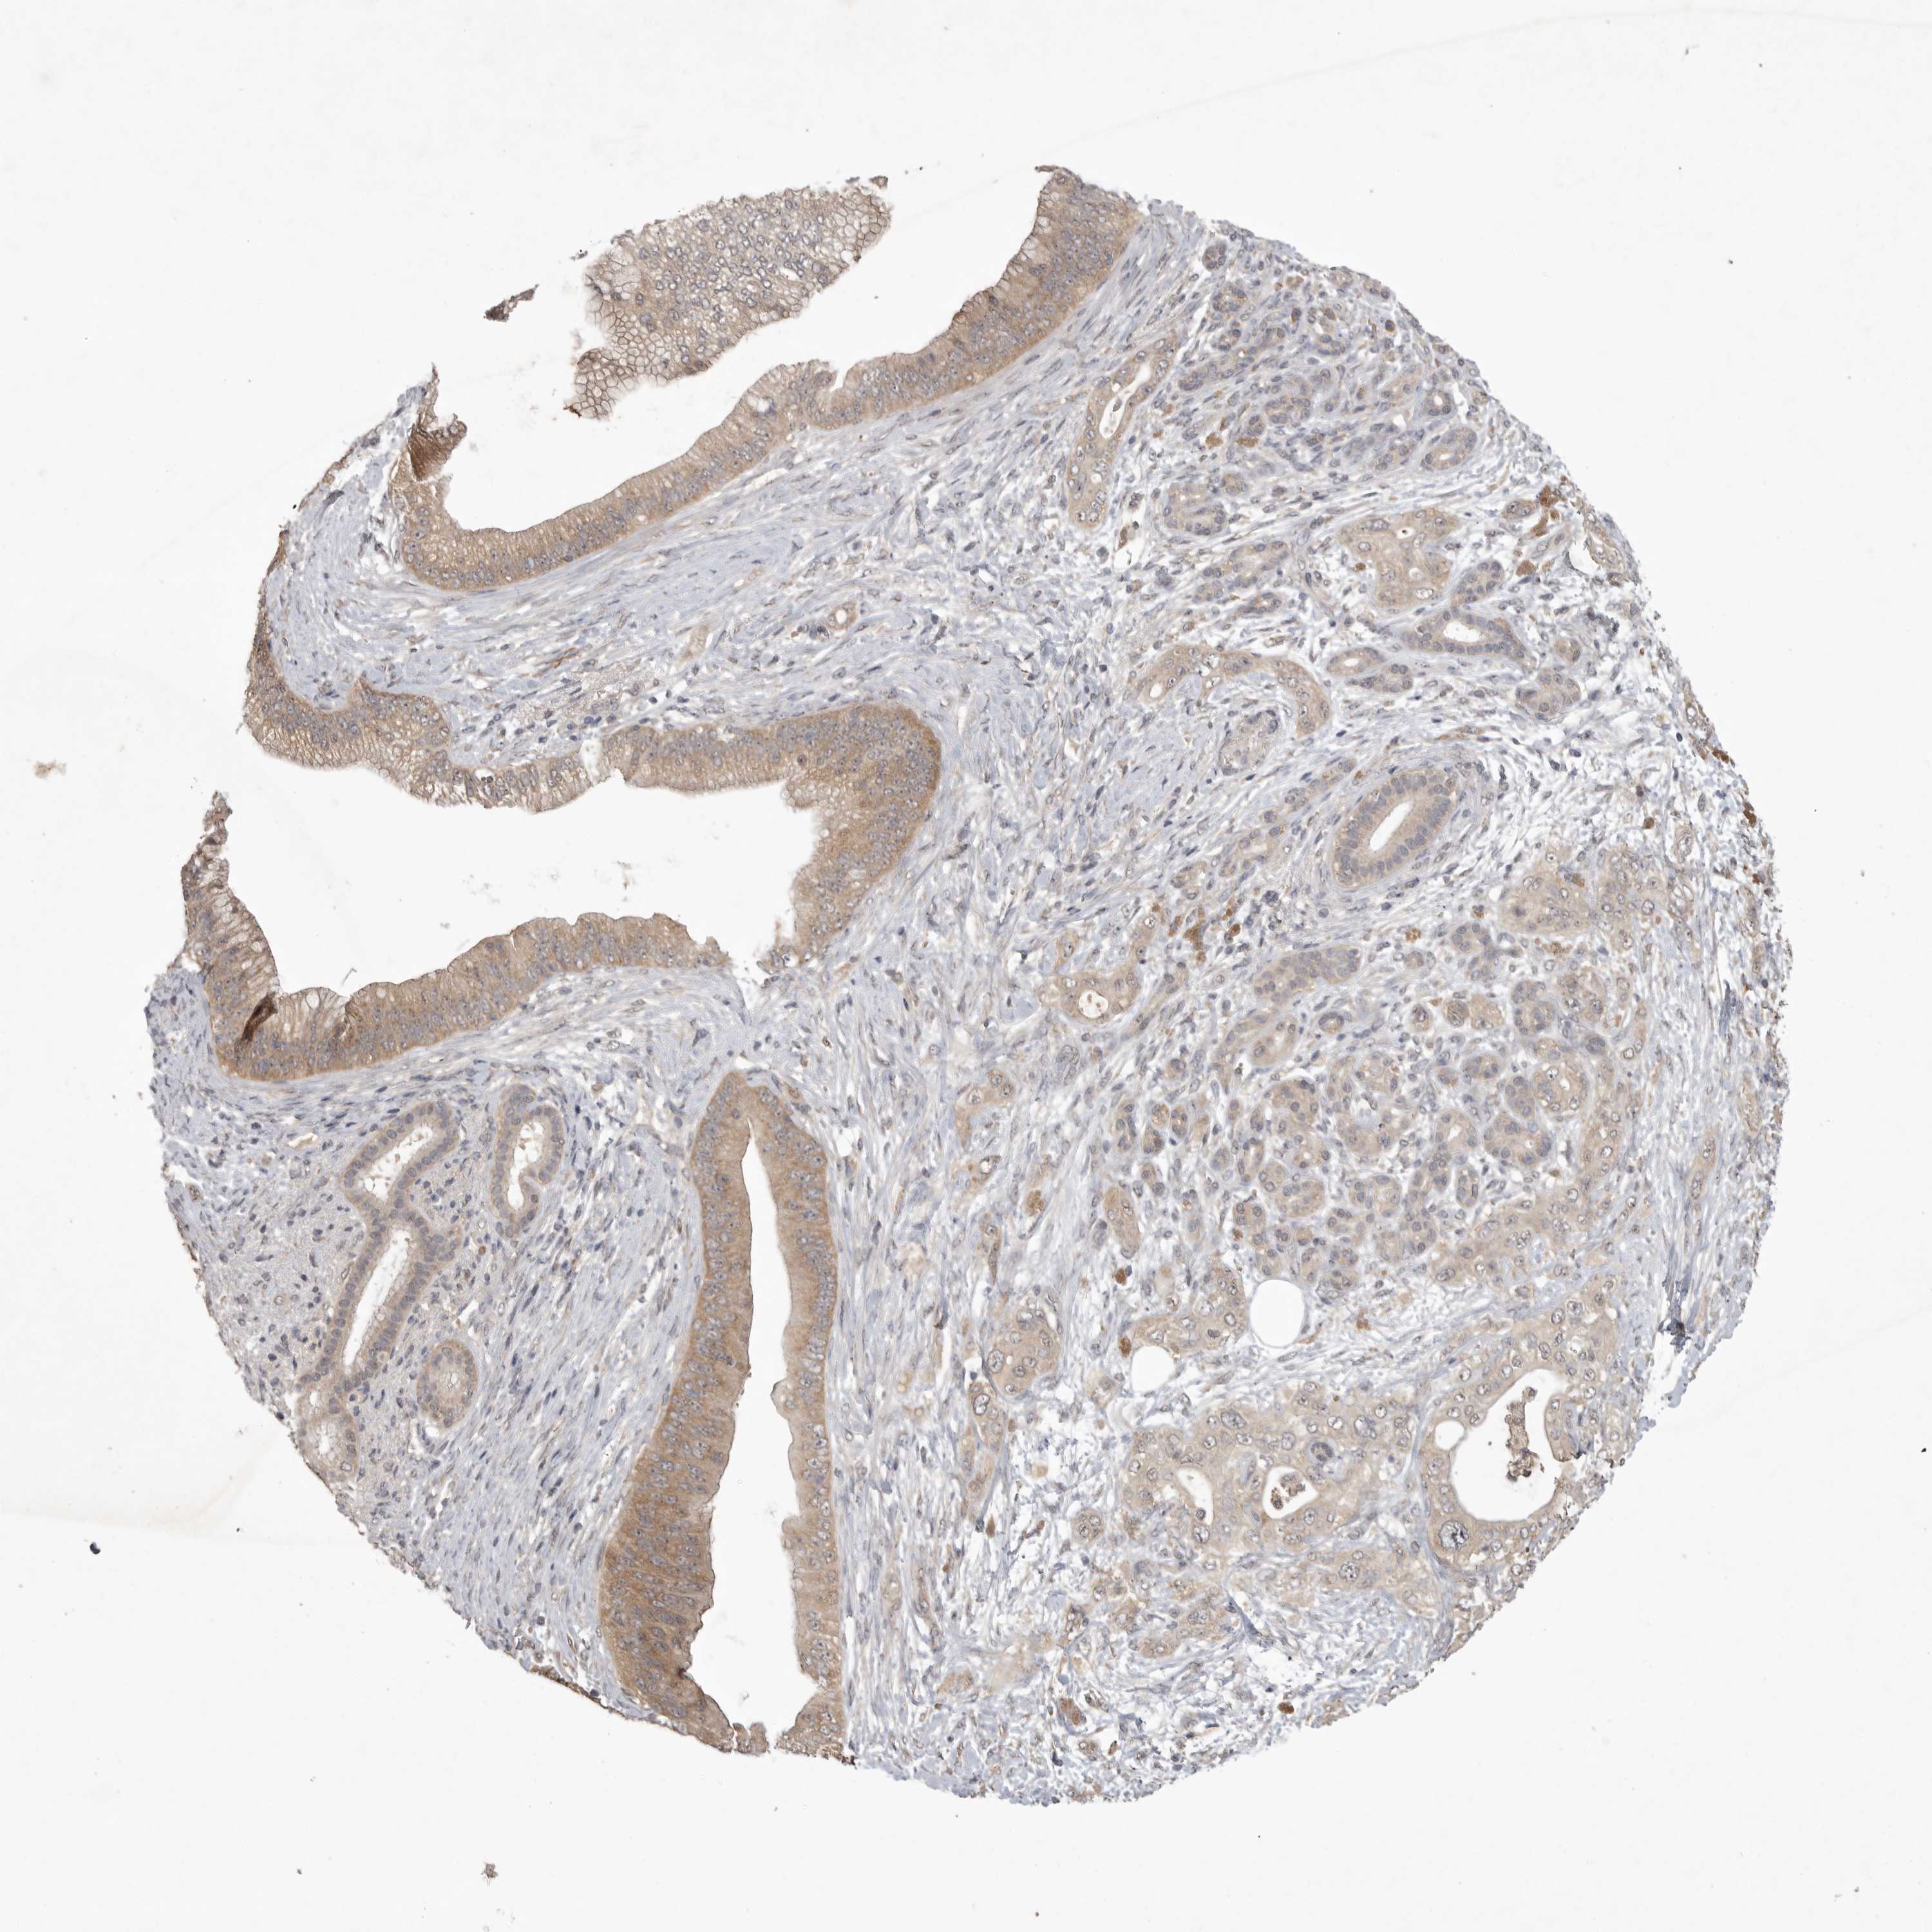

PANCREATIC CANCER - Protein expressioni

A mouse-over function shows sample information and annotation data. Click on an image to view it in a full screen mode. Samples can be filtered based on level of antibody staining by selecting one or several of the following categories: high, medium, low and not detected. The assay and annotation is described here.

Note that samples used for immunohistochemistry by the Human Protein Atlas do not correspond to samples in the TCGA dataset.

Antibody stainingi

Antibody staining in the annotated cell types in the current human tissue is reported as not detected, low, medium, or high, based on conventional immunohistochemistry profiling in selected tissues. This score is based on the combination of the staining intensity and fraction of stained cells.

Each image is clickable and will lead to virtual microscopy that enables deeper exploration of all samples and also displays staining intensity scores, fraction scores and subcellular localization as well as patient and tissue information for each sample.

Antibody HPA025019

Antibody HPA029553

Adenocarcinoma, NOS